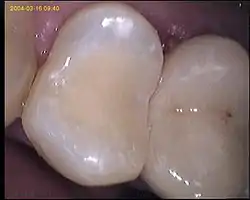

Composites en odontología

Se utilizan en odontología para obturar dientes. A diferencia de la amalgama de plata, que requiere para su obturación unas cavidades especiales (cavidades de Black), el composite se adhiere micromecánicamente a la superficie del diente sin depender de la cavidad. Las resinas compuestas constan de un componente orgánico polimérico llamado matriz, y un componente inorgánico que actúa como mineral de relleno.

Una de las principales ventajas de los composites o resinas compuestas, es su forma de unión a la estructura dental, mediante la utilización de sistemas adhesivos, los cuales permiten lograr un sellado hermético entre la resina y el diente favoreciendo la longevidad de una restauración u obturación dental.[3]

El estado inicial de estos materiales es una consistencia plástica, que permite su manipulación para la confección de una restauración dental, y cambia a un estado rígido mediante el proceso de polimerización. Durante la polimerización, la resina se contrae debido a que los monómeros que forman la matriz orgánica, se encuentran separados y mientras polimerizan acortan la distancia entre ellos, provocando que el material en estado rígido tenga un volumen menor al que ocupaba inicialmente. Esta es, sin duda, la gran desventaja que desde sus inicios presentaron los composites y es lo que se denomina contracción de polimerización,[4] sin embargo gracias a grandes avances en la evolución de los materiales dentales, se ha tratado de modificar el proceso de polimerización para así mejorar el comportamiento del material en las restauraciones dentales.